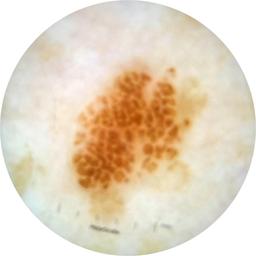

image_type dermoscopic

diagnosis_1 Benign

diagnosis_confirm_type single image expert consensus

fitzpatrick_skin_type I

anatom_site_1 Upper extremity

acquisition_day 162

age_approx 40